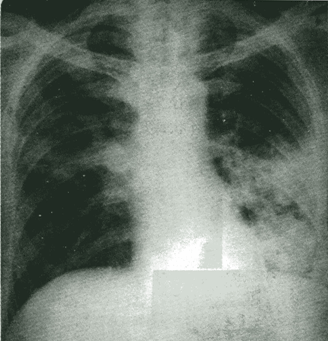

1.后前位可见心缘正常弧段消失,心影向两侧扩大,呈“普大”型或球形。

2.多数病例肺血管纹理正常,部分病例可伴有不同程度的上腔静脉扩张。

3.心缘搏动减弱或消失,而心包外的主动脉搏动正常。(透视)